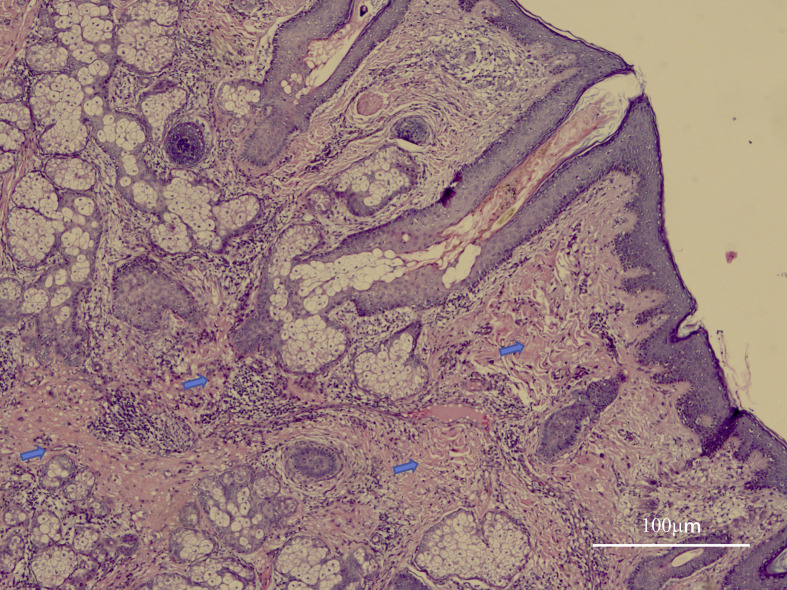

Case presentation: A 25-year-old man exhibited extensive skin folding on his face, a gyrus-like scalp, depressed nasolabial folds, and keloids. Symptoms began at 18 years of age, progressing insidiously. Additionally, he experienced clubbing of fingers and toes, joint pain, muscle soreness, and hyperhidrosis. Radiographic examinations revealed thickened bone and cystic regions. Diagnosed with complete primary PDP and facial keloid scars, he underwent skin dermabrasion, biopsies, and a comprehensive treatment involving, botulinum toxin injections, 5-fluorouracil, and a carbon dioxide lattice laser.